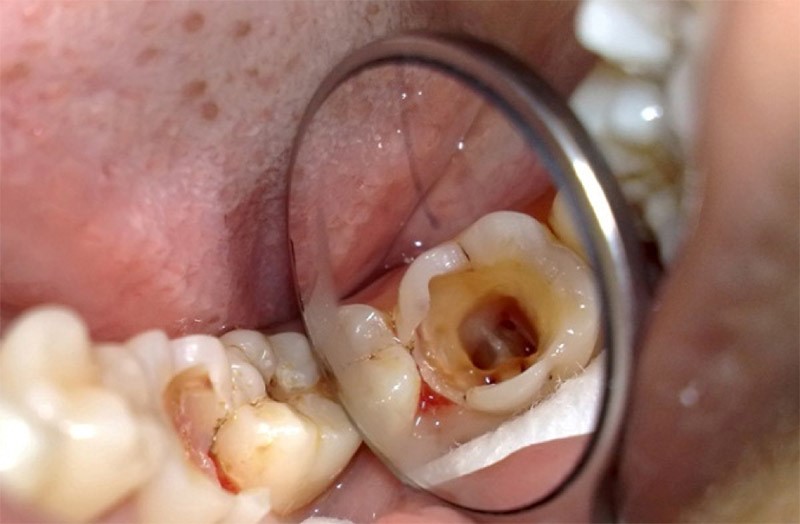

(Trám răng sâu sẽ có lấy tủy nếu tủy đã bị viêm, răng bị sâu nghiêm trọng)(**)